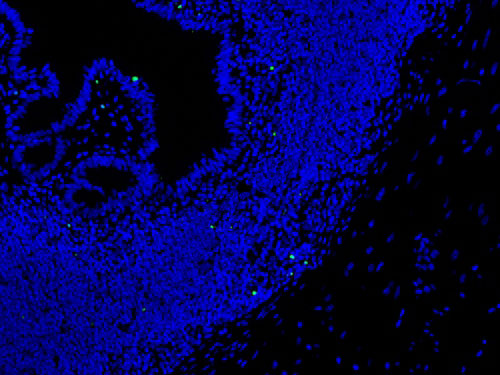

實(shí)驗(yàn)結(jié)果展示:

TUNEL(熒光)檢測(cè)-小鼠腸